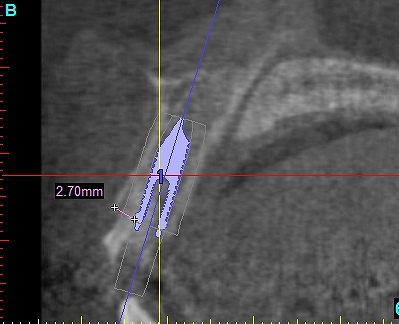

抜歯を行いました

即時インプラント埋入を行っています

術前の審査になります